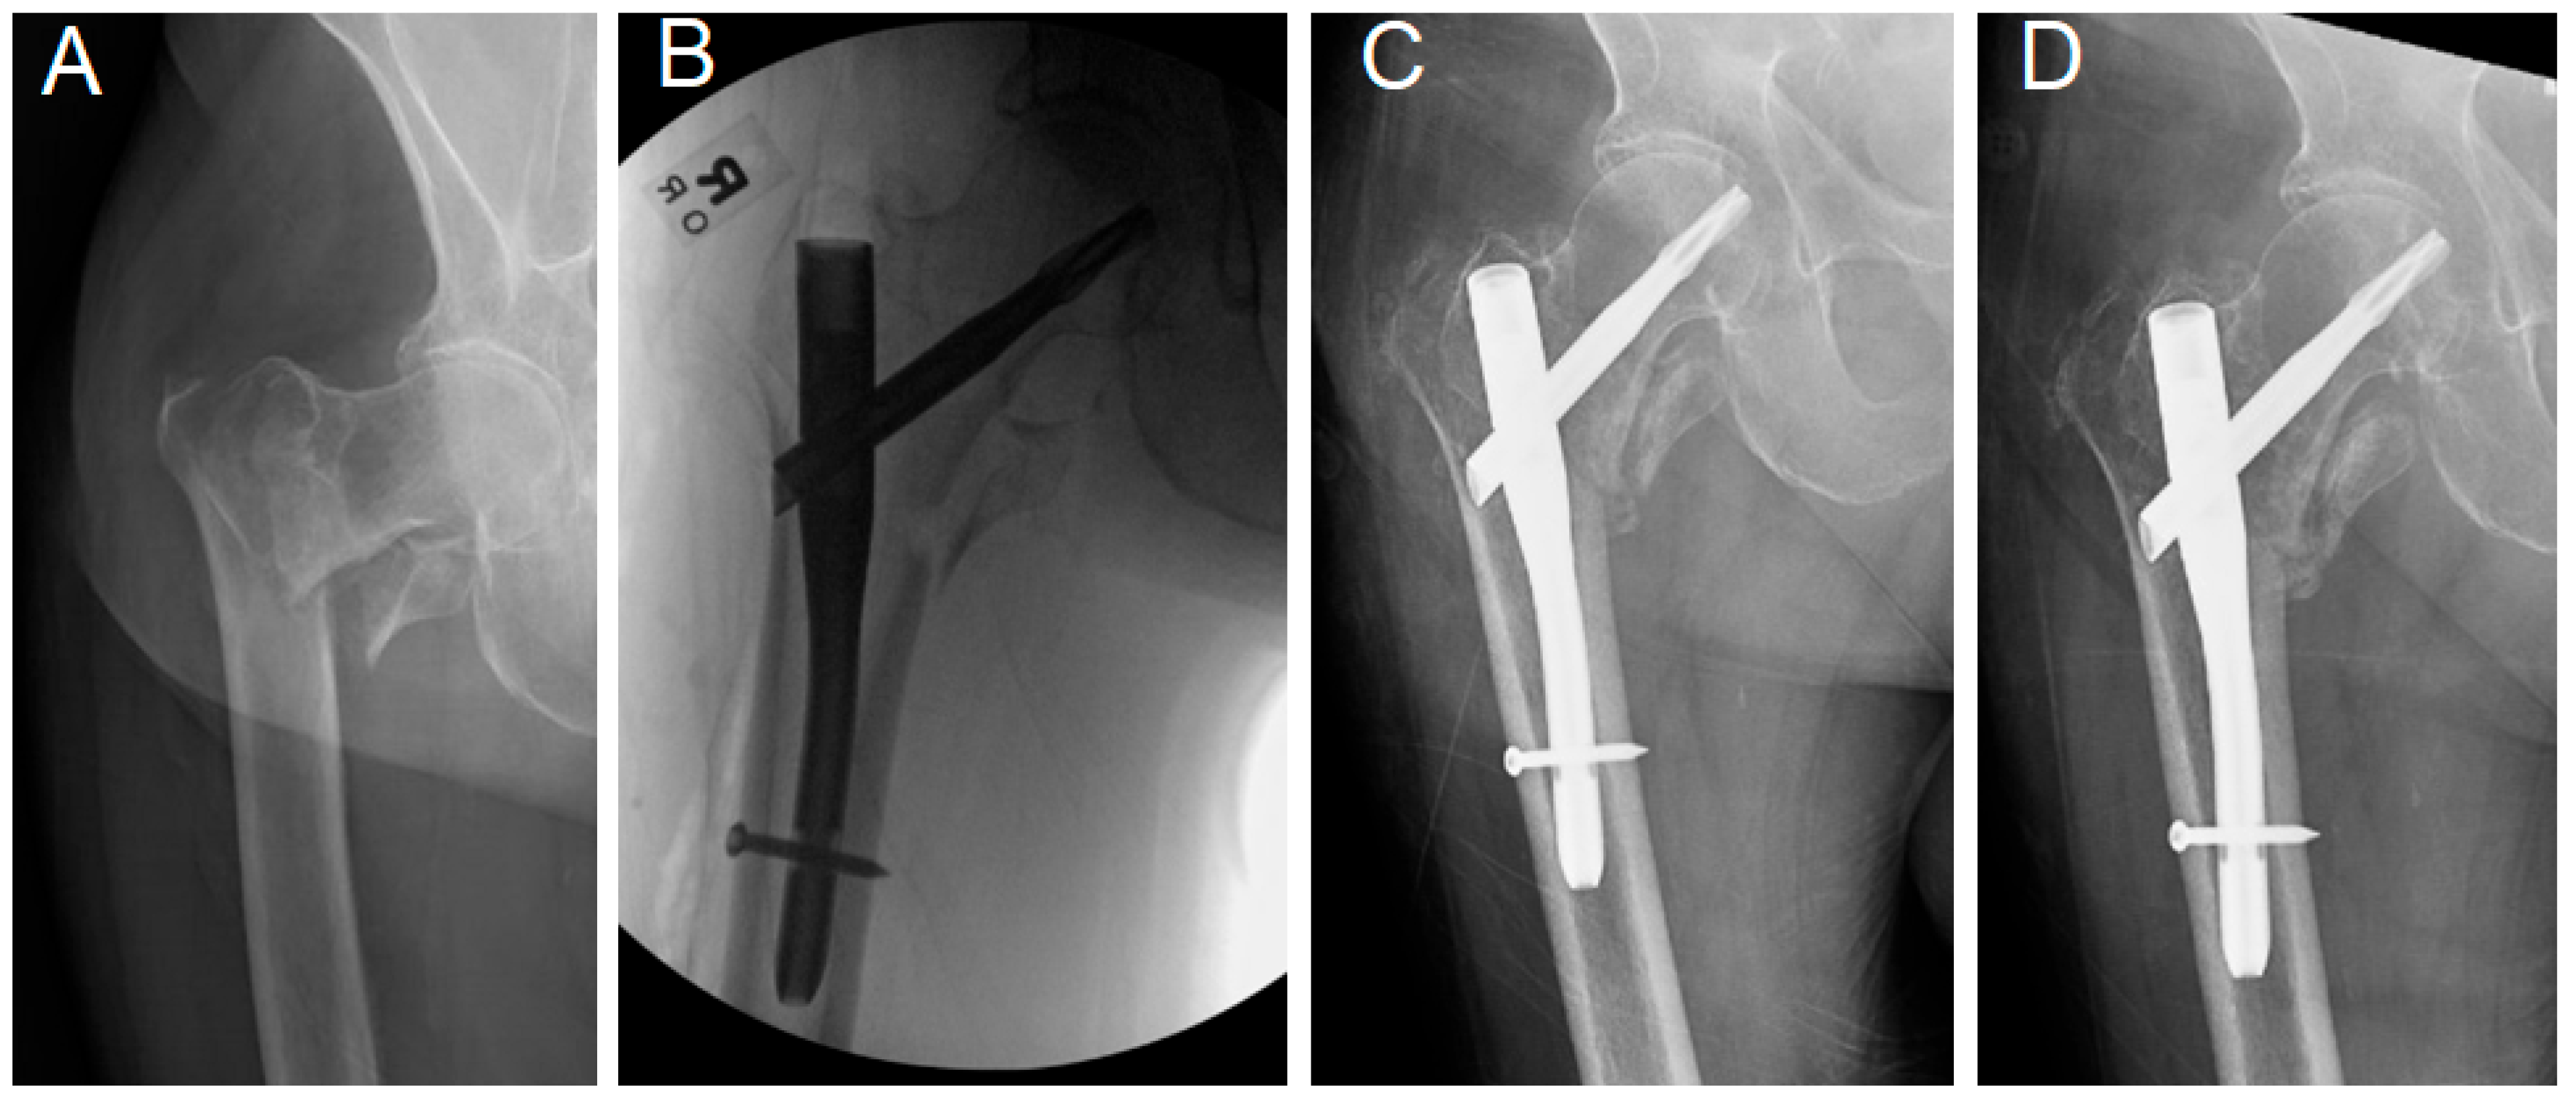

- Engagement of the lateral aspect of the lag device past the lateral cortex. A lag device was identified as “engaged” when both the superolateral and inferolateral borders of the device protruded freely outside the lateral femoral cortex in the intraoperative radiographs. This measurement was particularly made in the intraoperative radiograph to document the status of lag device engagement before any weight bearing and potential fracture collapse, to judge the utilized surgical technique.

- Integrity of the proximal femoral lateral cortex: The proximal femoral lateral wall, where the lateral end of the lag device engages, was assessed in the preoperative, intraoperative, and immediate postoperative X-rays or CT scan. Lateral wall incompetency was considered if any lateral wall breakage or fissure fracture was noticed.